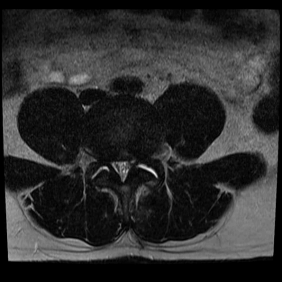

Cerca de cinco dias após a cirurgia, o paciente começou a apresentar piora clínica, evoluindo com lombalgia e parestesia contínua no MIE, e foi novamente submetido a exames de imagem para avaliação, A nova RM mostrou desidratação discal em L4-L5 e L5-S1, com presença de fissura anelar fibrosa periférica, além de discreto abaulamento discal difuso em L4-L5 e compressão da face ventral do saco dural e redução das bases foraminais, em contato discal com a raiz emergente esquerda de L4. Também foram observadas alterações degenerativas nas articulações interfacetárias lombares, mais claramente em L4-L5, onde havia edema periarticular. Por conseguinte, o paciente continuou o tratamento com sintomáticos para aliviar suas queixas, enquanto aguardava o agendamento e a realização de uma nova cirurgia.

Figura 2. RM de coluna lombar (sequência T2 ponderada, corte axial no nível L4-L5) evidenciando material de sinal heterogêneo no recesso lateral esquerdo, determinando compressão da raiz nervosa correspondente. Observa-se redução do espaço discal e alteração do sinal do disco intervertebral, compatíveis com degeneração discal..